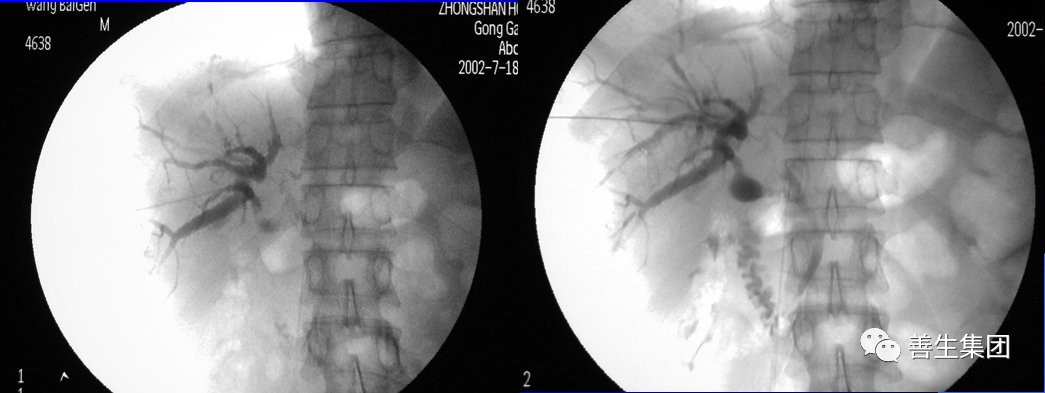

高位梗阻PTC示肝门部梗阻,左右肝管分别受侵犯

高位梗阻胆管癌患者

穿刺右肝管分别穿刺左右肝管,Y型放置2枚支架型内支架